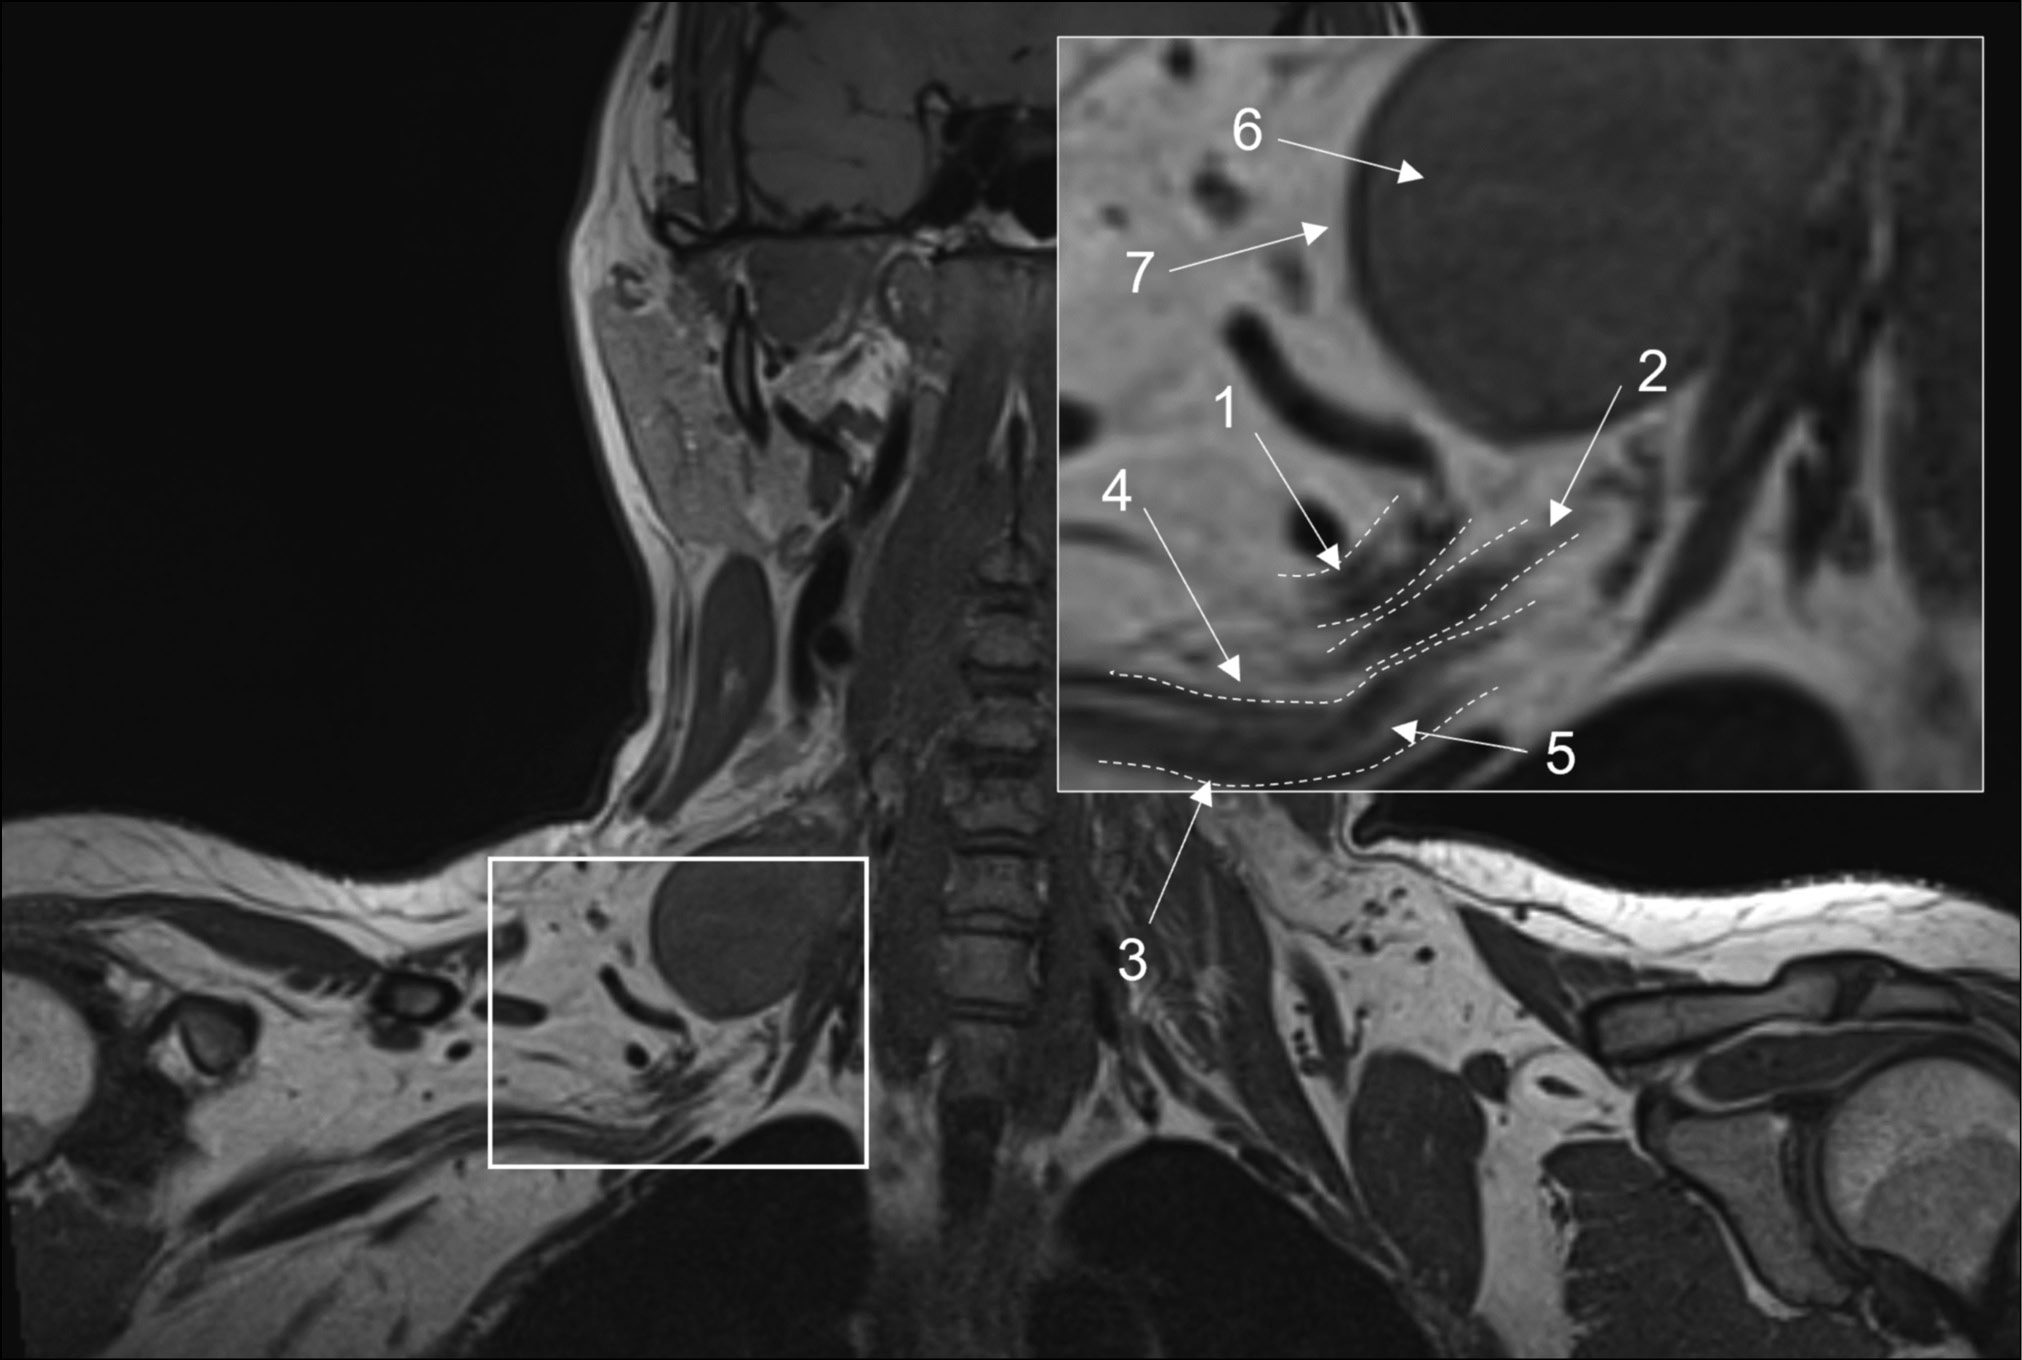

T1-weighted images

These images are essential for neurography and can be acquired using spin echo or free fluid suppression inversion recovery sequences in the axial plane for extremity nerves and the coronal plane for plexuses. The length of the echo complex varies from three to eight for 2D images and from 33 to 68 for 3D images. A scanning plane resolution of 0.3 to 0.4 mm ensures optimal visibility of intraneural fat, epineurium thickening, and elimination of perineural fat due to mass lesion development or fibrosis (Fig. 1) [28]. Furthermore, these images are critical for determining fatty infiltration and muscular atrophy. They are also less susceptible to motion and magnetic susceptibility aberrations and can typically detect edema, tract interruption, or changes in cross-sectional nerve configuration due to compression [3].

Fig. 1. Magnetic resonance imaging of the brachial plexuses in 3D-T1 mode. A coronal projection: (1) the upper trunk, (2) the middle trunk, (3) the lower trunk, (4) the perineural fatty tissue, (5) the endoneurial fat, (6) a mass lesion (schwannoma), and (7) the intact fatty tissue around the lesion.